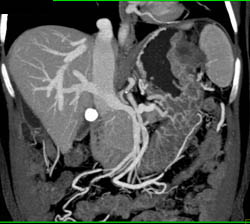

Gastric Adenocarcinoma